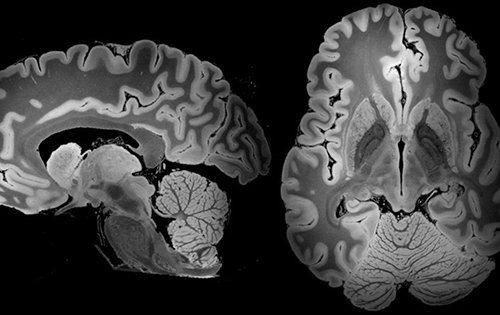

МРТ головного мозга: показания и результаты

Раздел: Визуальный дайджест